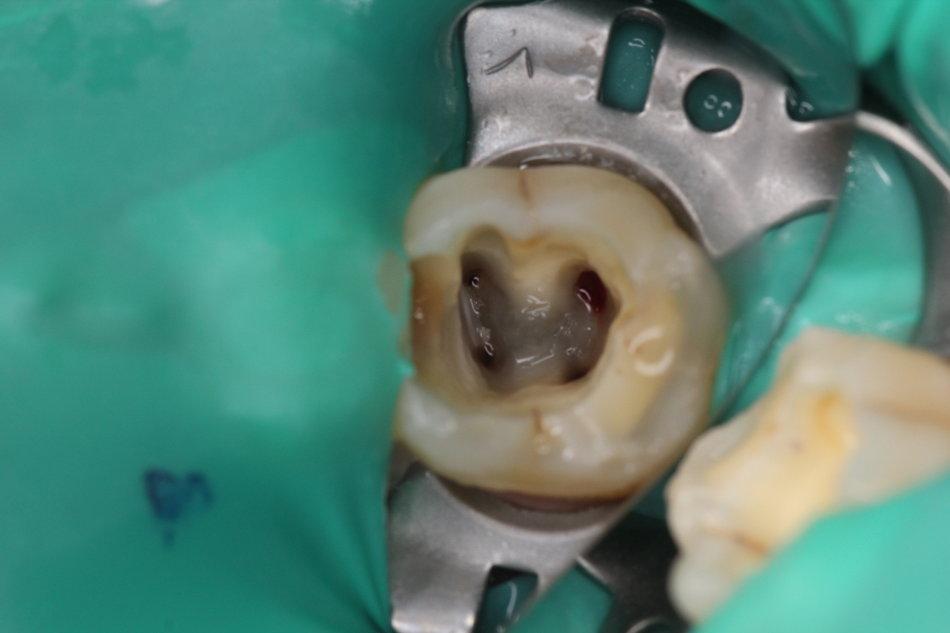

现在很多人都会蛀牙,然后很多人发现蛀牙的时候,往往都是比较严重了,需要进行根管治疗——也就是要截取牙神经。

由于牙齿没有了牙神经,因为牙齿的血管和神经是在一起的,牙神经被杀死,牙齿的血管也就被破坏掉了,牙齿内部的血液循环就没有了,只在牙齿外部,通过牙周膜内的血管有血液循环,这样牙齿的营养就比较缺乏,质地就会变脆,加上在牙齿杀神经的治疗过程中,需要磨掉许多牙齿组织,所以牙齿的强度就进一步降低,这样的牙齿容易劈裂,所以一定不要用杀过神经牙咬硬物,以避免牙齿劈裂。

不能。一般需要进行根管治疗的牙齿,说明都已经进入了感染期,牙齿是会有较大的疼痛感的。如果不进行根管治疗,炎症只会越来越厉害,最终有可能导致牙齿真的保不住——松动,掉落。